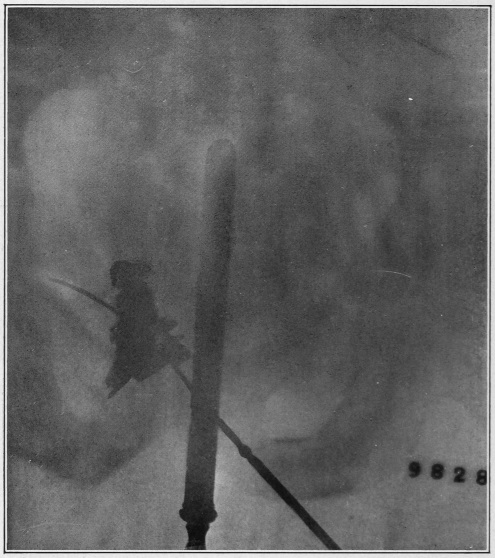

Nine Radiograph Illustrations Showing Mucus Channels and Cavities200

When disease exists we simply desire to open the contracted or obstructed canal. What can be better, in a therapeutic line, than the kindly distending influence of warm water to overcome the spasmodic closure of the diseased tube? In addition to the gentle dilatation the injected water occasions, the water creates or calls into activity the lost nervous impulse to evacuate, which impulse is a step toward the restoration of the lost normality.